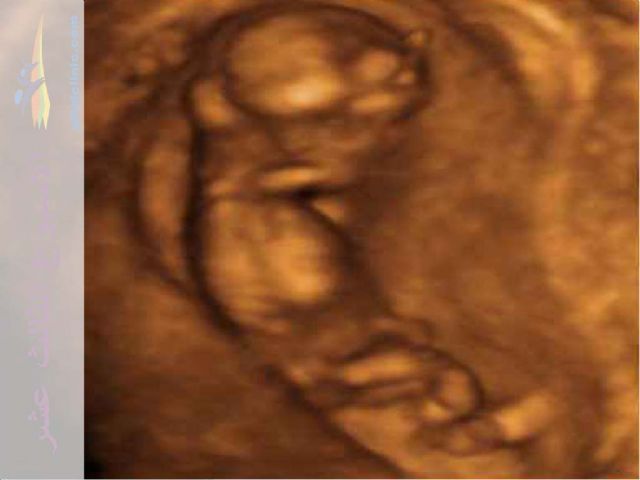

5/9/2014• الحمل في الأسبوع الثالث عشر :

- يكون طول الجنين 8 سم و وزنه 1 أونصة .